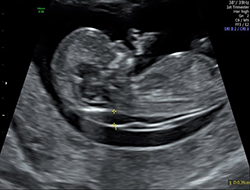

Nuchal translucency nt is the sonographic appearance of a collection of fluid under the skin behind the fetal neck in the first trimester of pregnancy. Requirements there are two requirements for the certification process. The term translucency is used irrespective of whether it is septated or not and whether it is confined to the neck or envelopes the whole fetus. Nuchal translucency nt is the sonographic appearance of a collection of fluid under the skin behind the fetal neck in the first trimester of pregnancy.

It will take between 20 to 40 minutes. The term translucency is used irrespective of whether it is septated or not and whether it is confined to the neck or envelopes the whole fetus. The nuchal translucency quality review was created to educate providers on how to obtain reproducible nuchal translucency measurements 2 provide a method to evaluate and track provider proficiency and 3 provide on going nuchal translucency quality review. First trimester screening includes an ultrasound exam to measure the size of the clear space in the tissue at the back of a babys neck nuchal translucency.